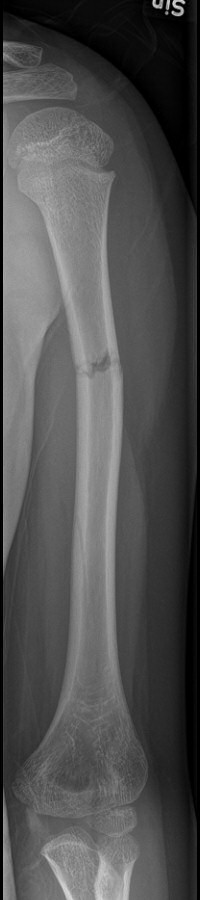

Fraktur humerusdiafys

1-årigt barn med diafysär humerusfraktur, fick vadd runt armen och linda runt kroppen i 3 veckor, därefter kliniskt läkt.